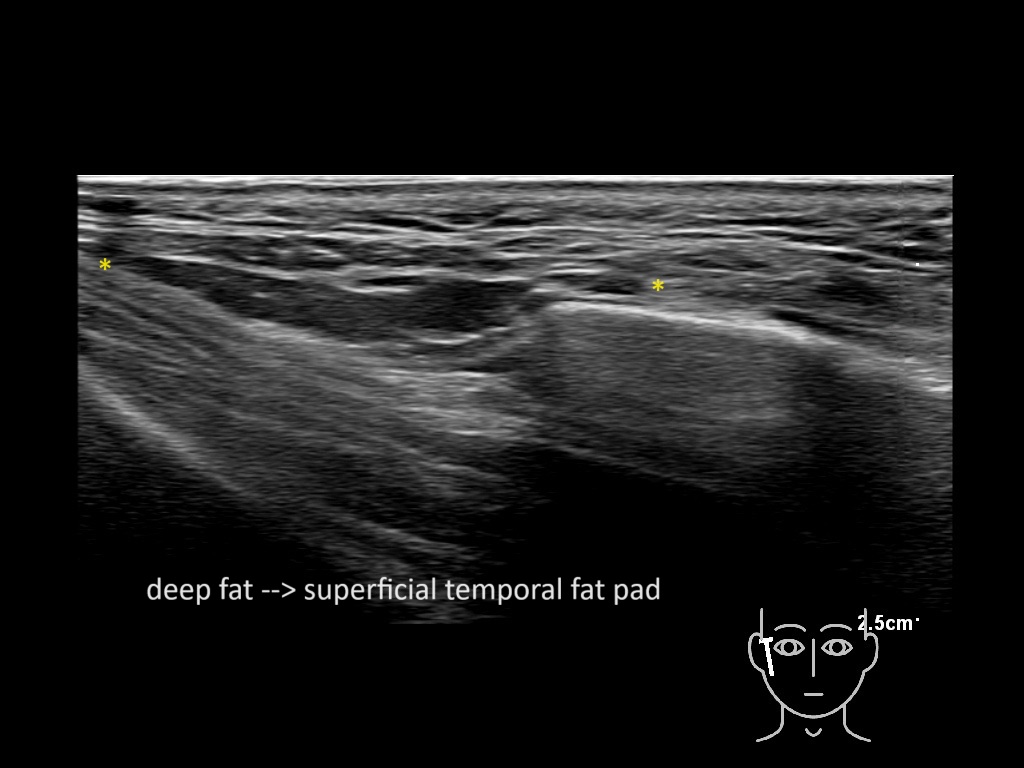

Filler behavior - Temple zygoma US

Study the first image to recognize the different layers. If you are sure about the layers, swipe to the second image to view the answer (if applicable).

Hover over an image to view the secondary image or click on the image title for more information.